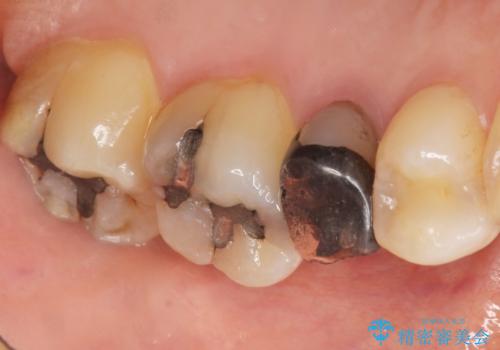

自然な見た目と咬み心地にご満足頂けました。

オフィスホワイトニングを行い、白くなった天然歯に合わせたシェード(お色味)でクラウンを作製しました。

モチベーションが上がり、他の銀歯もセラミックで治していきたいとご希望され、現在治療中です。

クラウンの種類:オールセラミッククラウン スタンダード